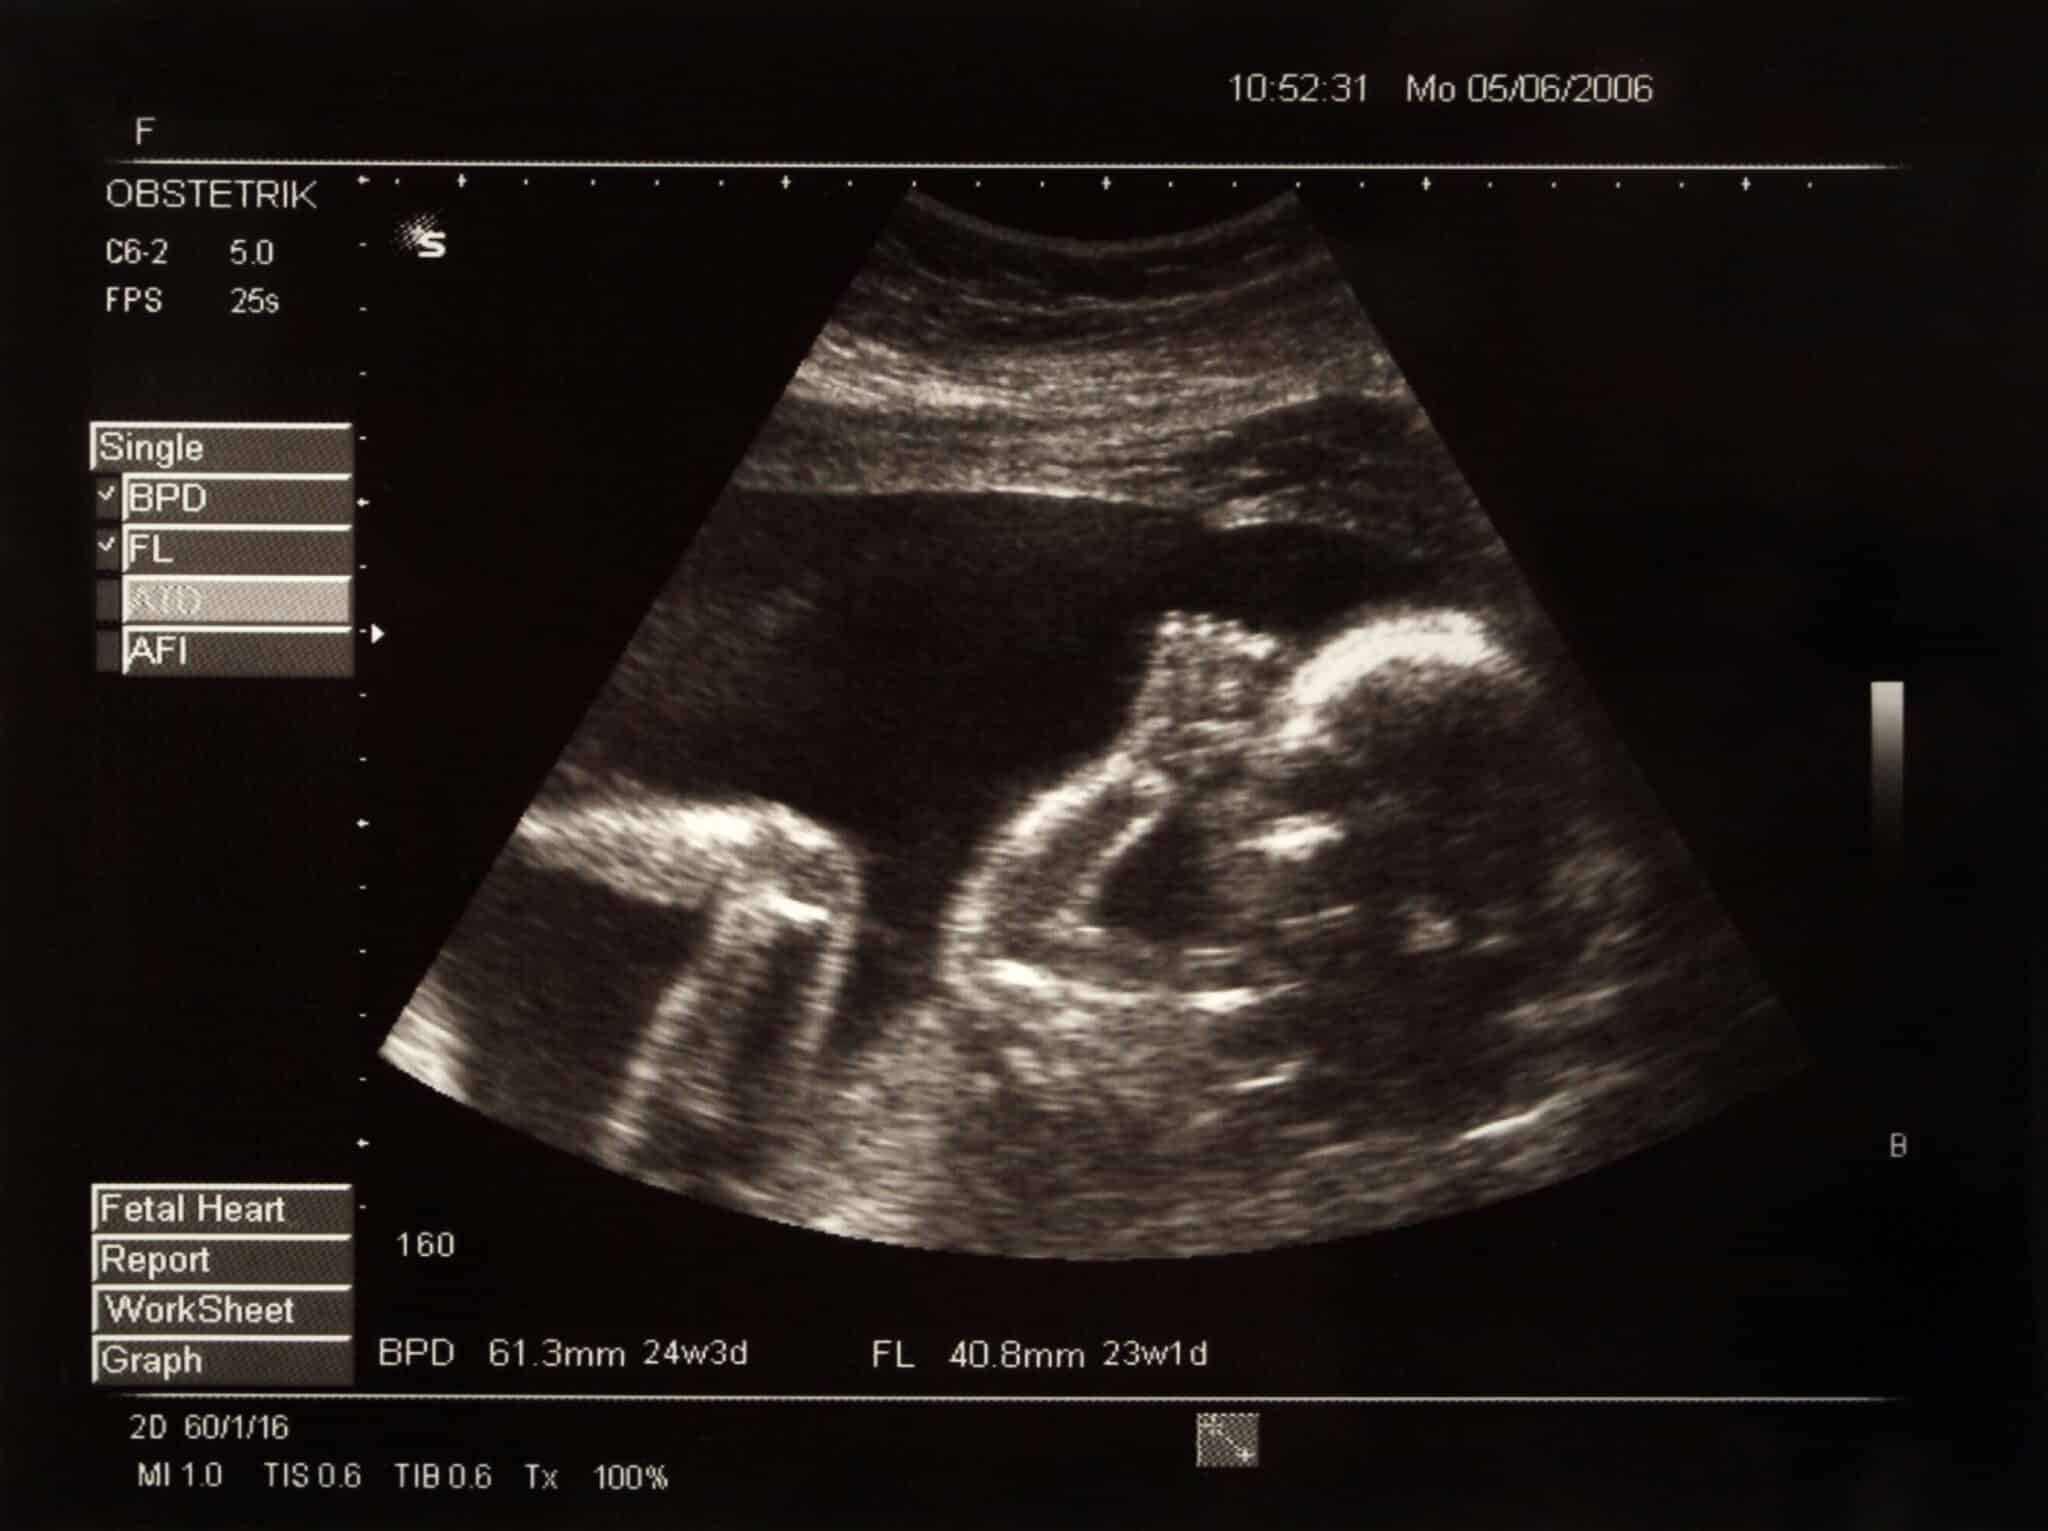

La 50enne congolese è arrivata negli USA 14 mesi fa, ed è stata visitata dai medici del pronto soccorso del SUNY Upstate Medical University lamentando forti crampi allo stomaco ed indigestione. I medici hanno scoperto che aveva un feto (praticamente n bambino di pietra) nella cavità addominale e la biometria fetale ha stimato un’età gestazionale di 28 settimane al momento della morte del feto. Il feto aveva le dimensioni di una lattuga.